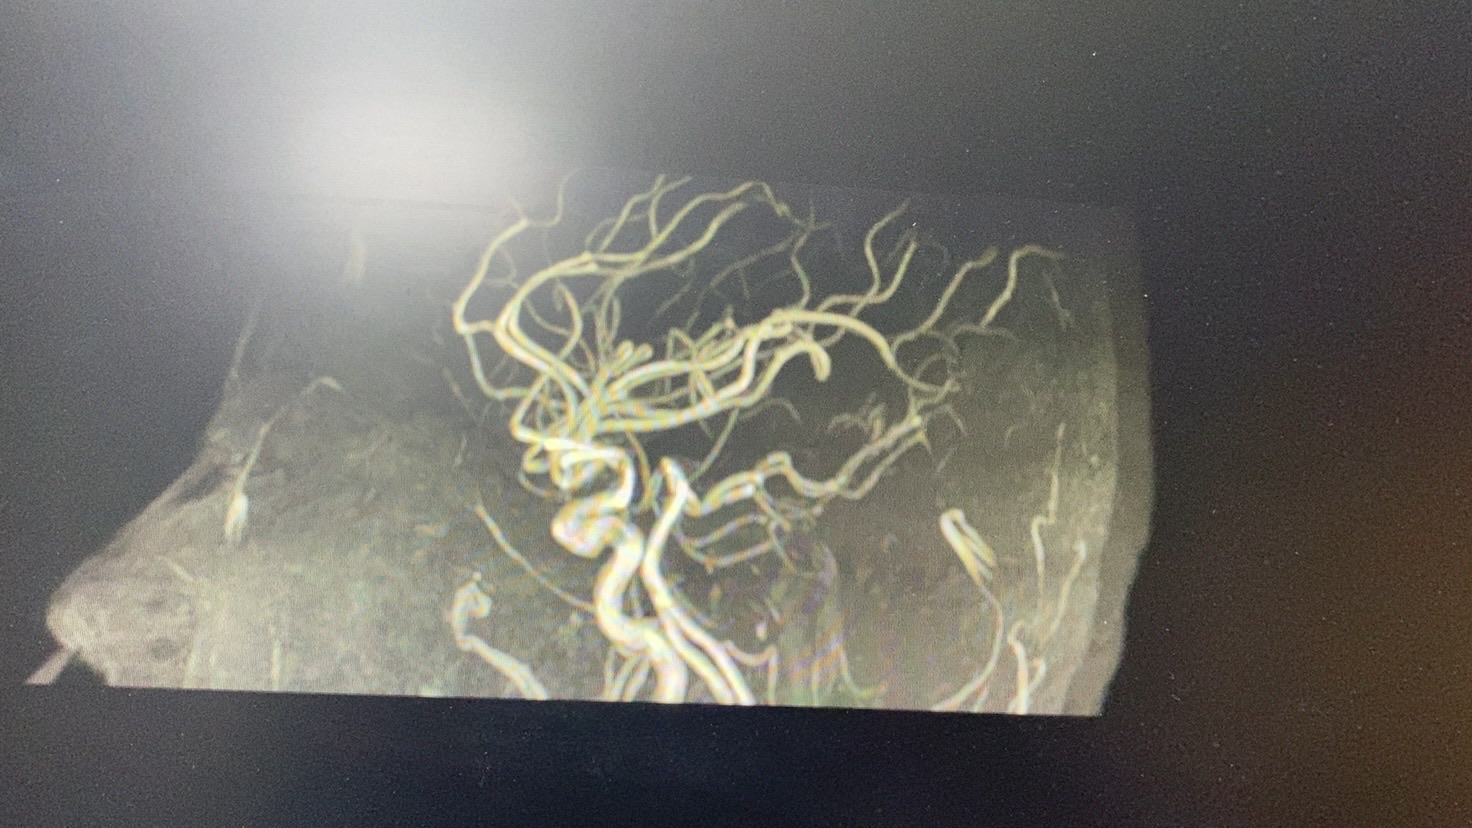

头MRA